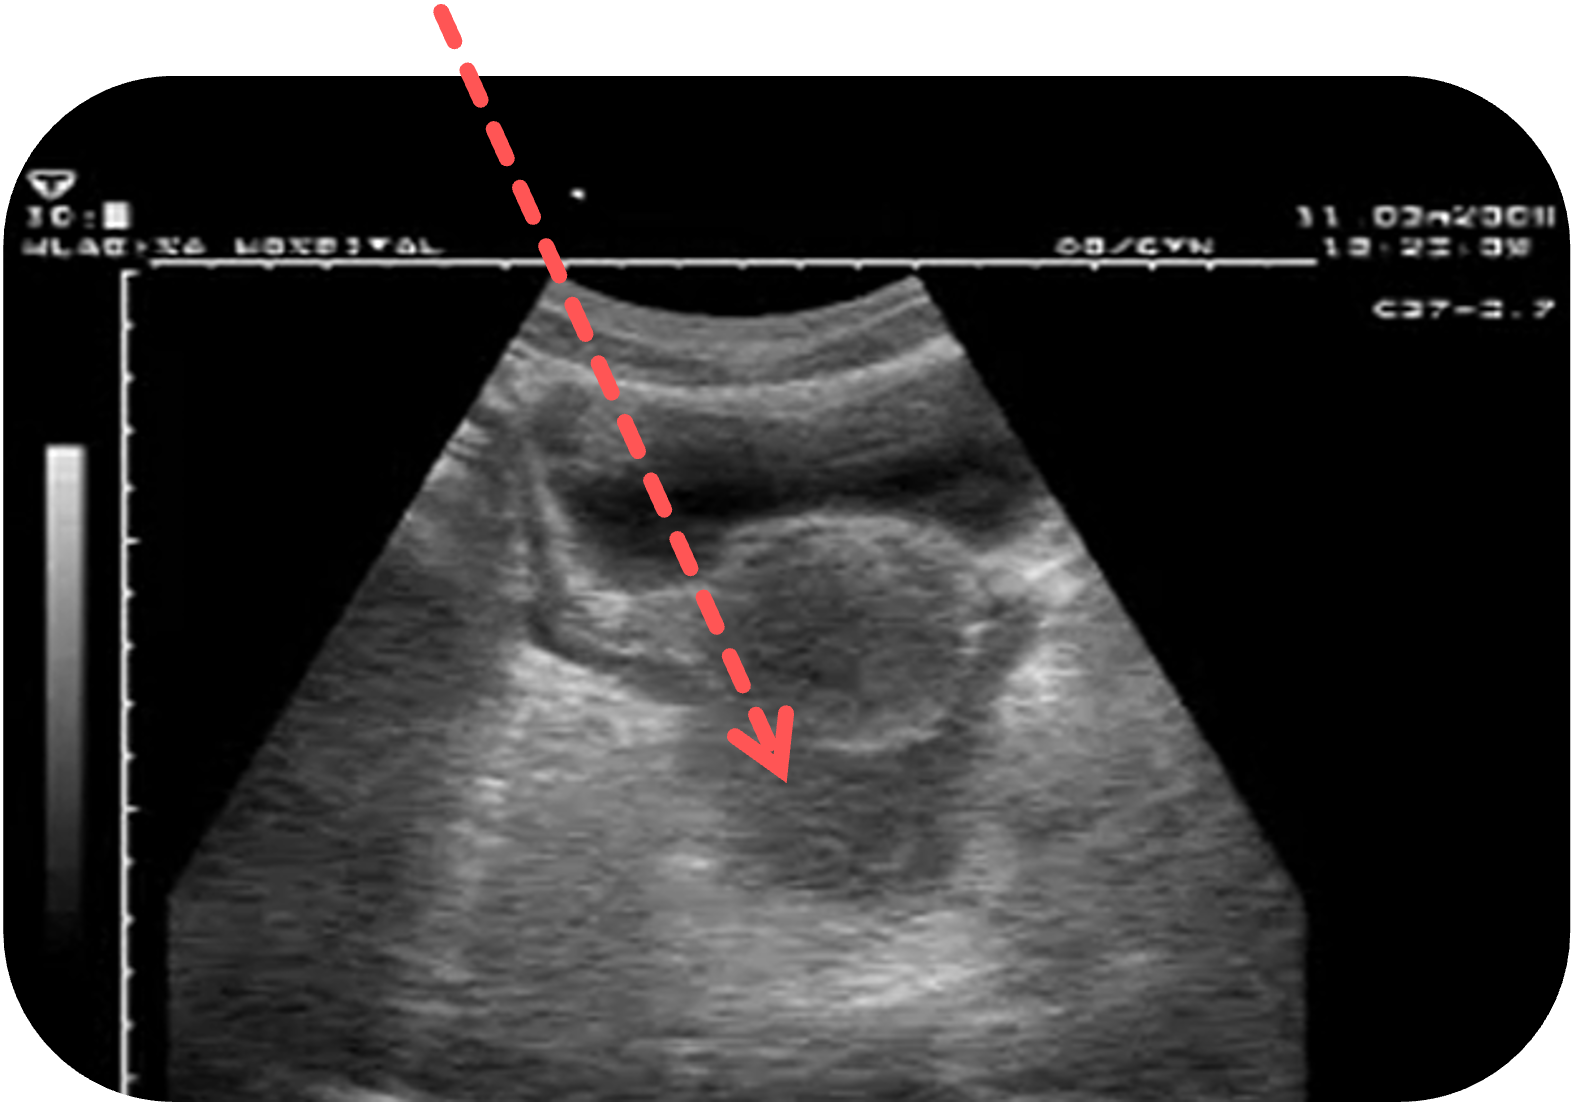

Frau:

Im Douglas-Raum, oft keilförmig

Screenshot aus Additional file 8 aus Heller, T., Wallrauch, C., Goblirsch, S. et al. Focused assessment with sonography for HIV-associated tuberculosis (FASH): a short protocol and a pictorial review. Crit Ultrasound J 4, 21 (2012). https://doi.org/10.1186/2036-7902-4-21. Es wurde der rote Pfeil ergänzt.

Freie Flüssigkeit bei der Frau

Freie Flüssigkeit im Douglas-Raum der Frau ist ein häufiger sonographischer Befund und kann sowohl physiologisch als auch pathologisch sein.

Pathologische Ursachen sind vielfältig und reichen von entzündlichen Prozessen (z. B. Adnexitis

In diesen Fällen kann die Flüssigkeit zunehmend inhomogen, echoreich oder mit Koagelstrukturen durchsetzt sein.

Screenshot aus Additional file 8 aus Heller, T., Wallrauch, C., Goblirsch, S. et al. Focused assessment with sonography for HIV-associated tuberculosis (FASH): a short protocol and a pictorial review. Crit Ultrasound J 4, 21 (2012). https://doi.org/10.1186/2036-7902-4-21. Es wurden die farbigen Markierungen und Beschriftungen ergänzt.

Auch bei intraabdominellen Blutungen (z. B. Milzruptur) oder Aszites